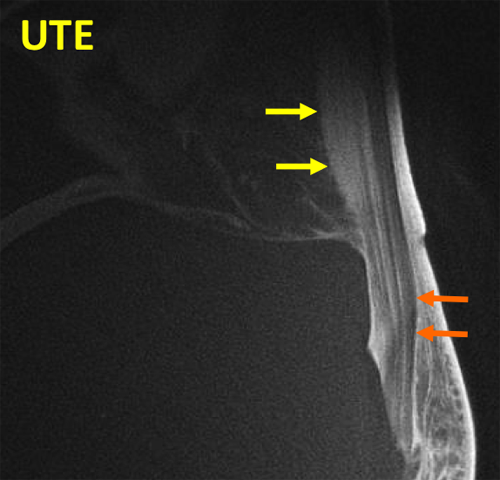

TMJ UTE

UTE sequence of the TMJ shows bright signal in the disc (arrows) and in the fibrocartilage covering the mandibular condyle (arrowhead).